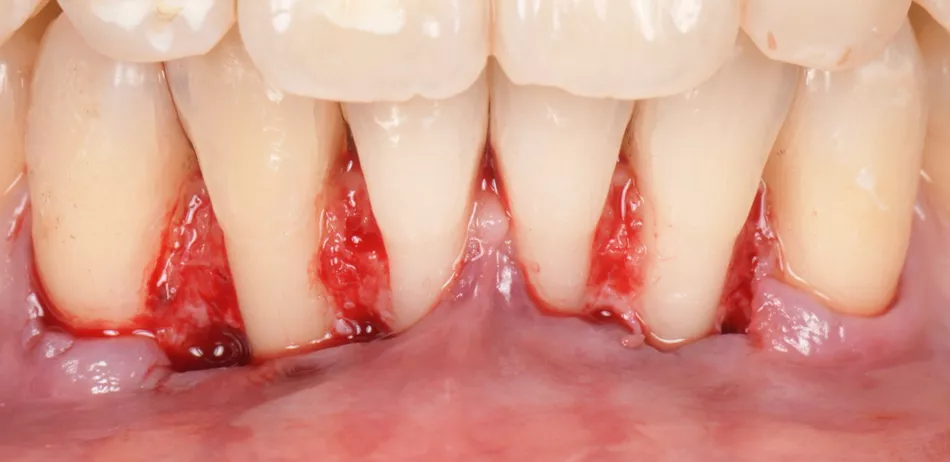

Root planing and surface conditioning with Straumann® Prefgel® for 2 minutes (Fig. 5).

The first connective tissue graft was placed on denuded roots of #43, #42, and #41 (Fig. 6), and the second on #31, #32 and #33 (Fig. 7), which all had previously been treated with Straumann® Emdogain®.